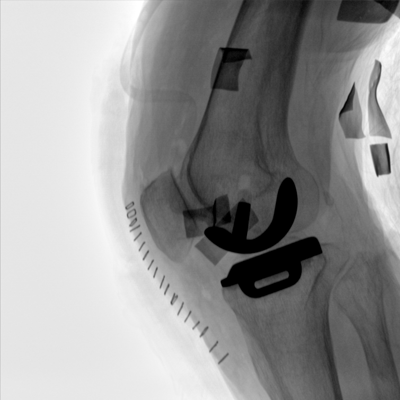

臨床適用科室:骨科、普通外科、矯形外科、創(chuàng)傷外科、泌尿外科、脊柱外科、疼痛外科、消化科、婦科等科室。

大尺寸動態(tài)平板探測器,高DQE、低噪聲、圖像清晰。采用多分辨率圖像增強(qiáng)處理技術(shù),不同部位不同圖像處理算法,滿足客戶多樣化的需求。

采用智能變頻脈沖透視技術(shù),優(yōu)化圖像質(zhì)量的同時降低輻射劑量,呵護(hù)醫(yī)患健康